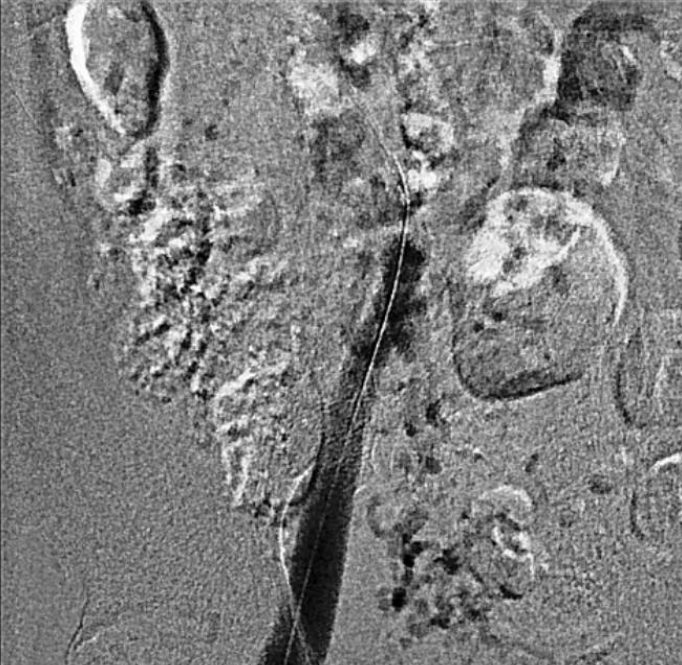

Venography showed occlusion of the right external and common iliac veins with collateral flow; popliteal and femoral veins were patent. A 6F sheath was placed in the right CFV, and a V-18 0.018 wire was advanced to the IVC. Attempts to traverse outside the prior left iliac-femoral stent for double-barrel reconstruction were unsuccessful, as the wire repeatedly entered the existing stent, likely due to complete apposition.The strategy was revised, and wiring into the IVC through a proximal stent strut was achieved. IVUS from the IVC to the RCFV confirmed severe compression at the right CIV ostium and proper wire position. A 10 ¡¿ 39 mm Abbott Omnilink balloon-expandable stent was deployed at the RCIV ostium and dilated to 10 atm. A kissing-balloon angioplasty was then performed with a 12 ¡¿ 40 mm Armada balloon from the LCIV and the RCIV balloon inflated simultaneously to 10 atm, restoring bifurcation geometry.A 14 ¡¿ 60 mm Bard Venovo stent was placed from the RCIV to the REIV and post-dilated with a 12 mm balloon to 10 atm. Final angiography showed widely patent, well-expanded stents with brisk antegrade flow into the IVC and no residual stenosis or thrombosis. Hemostasis was achieved with manual compression, and the procedure concluded without complications.